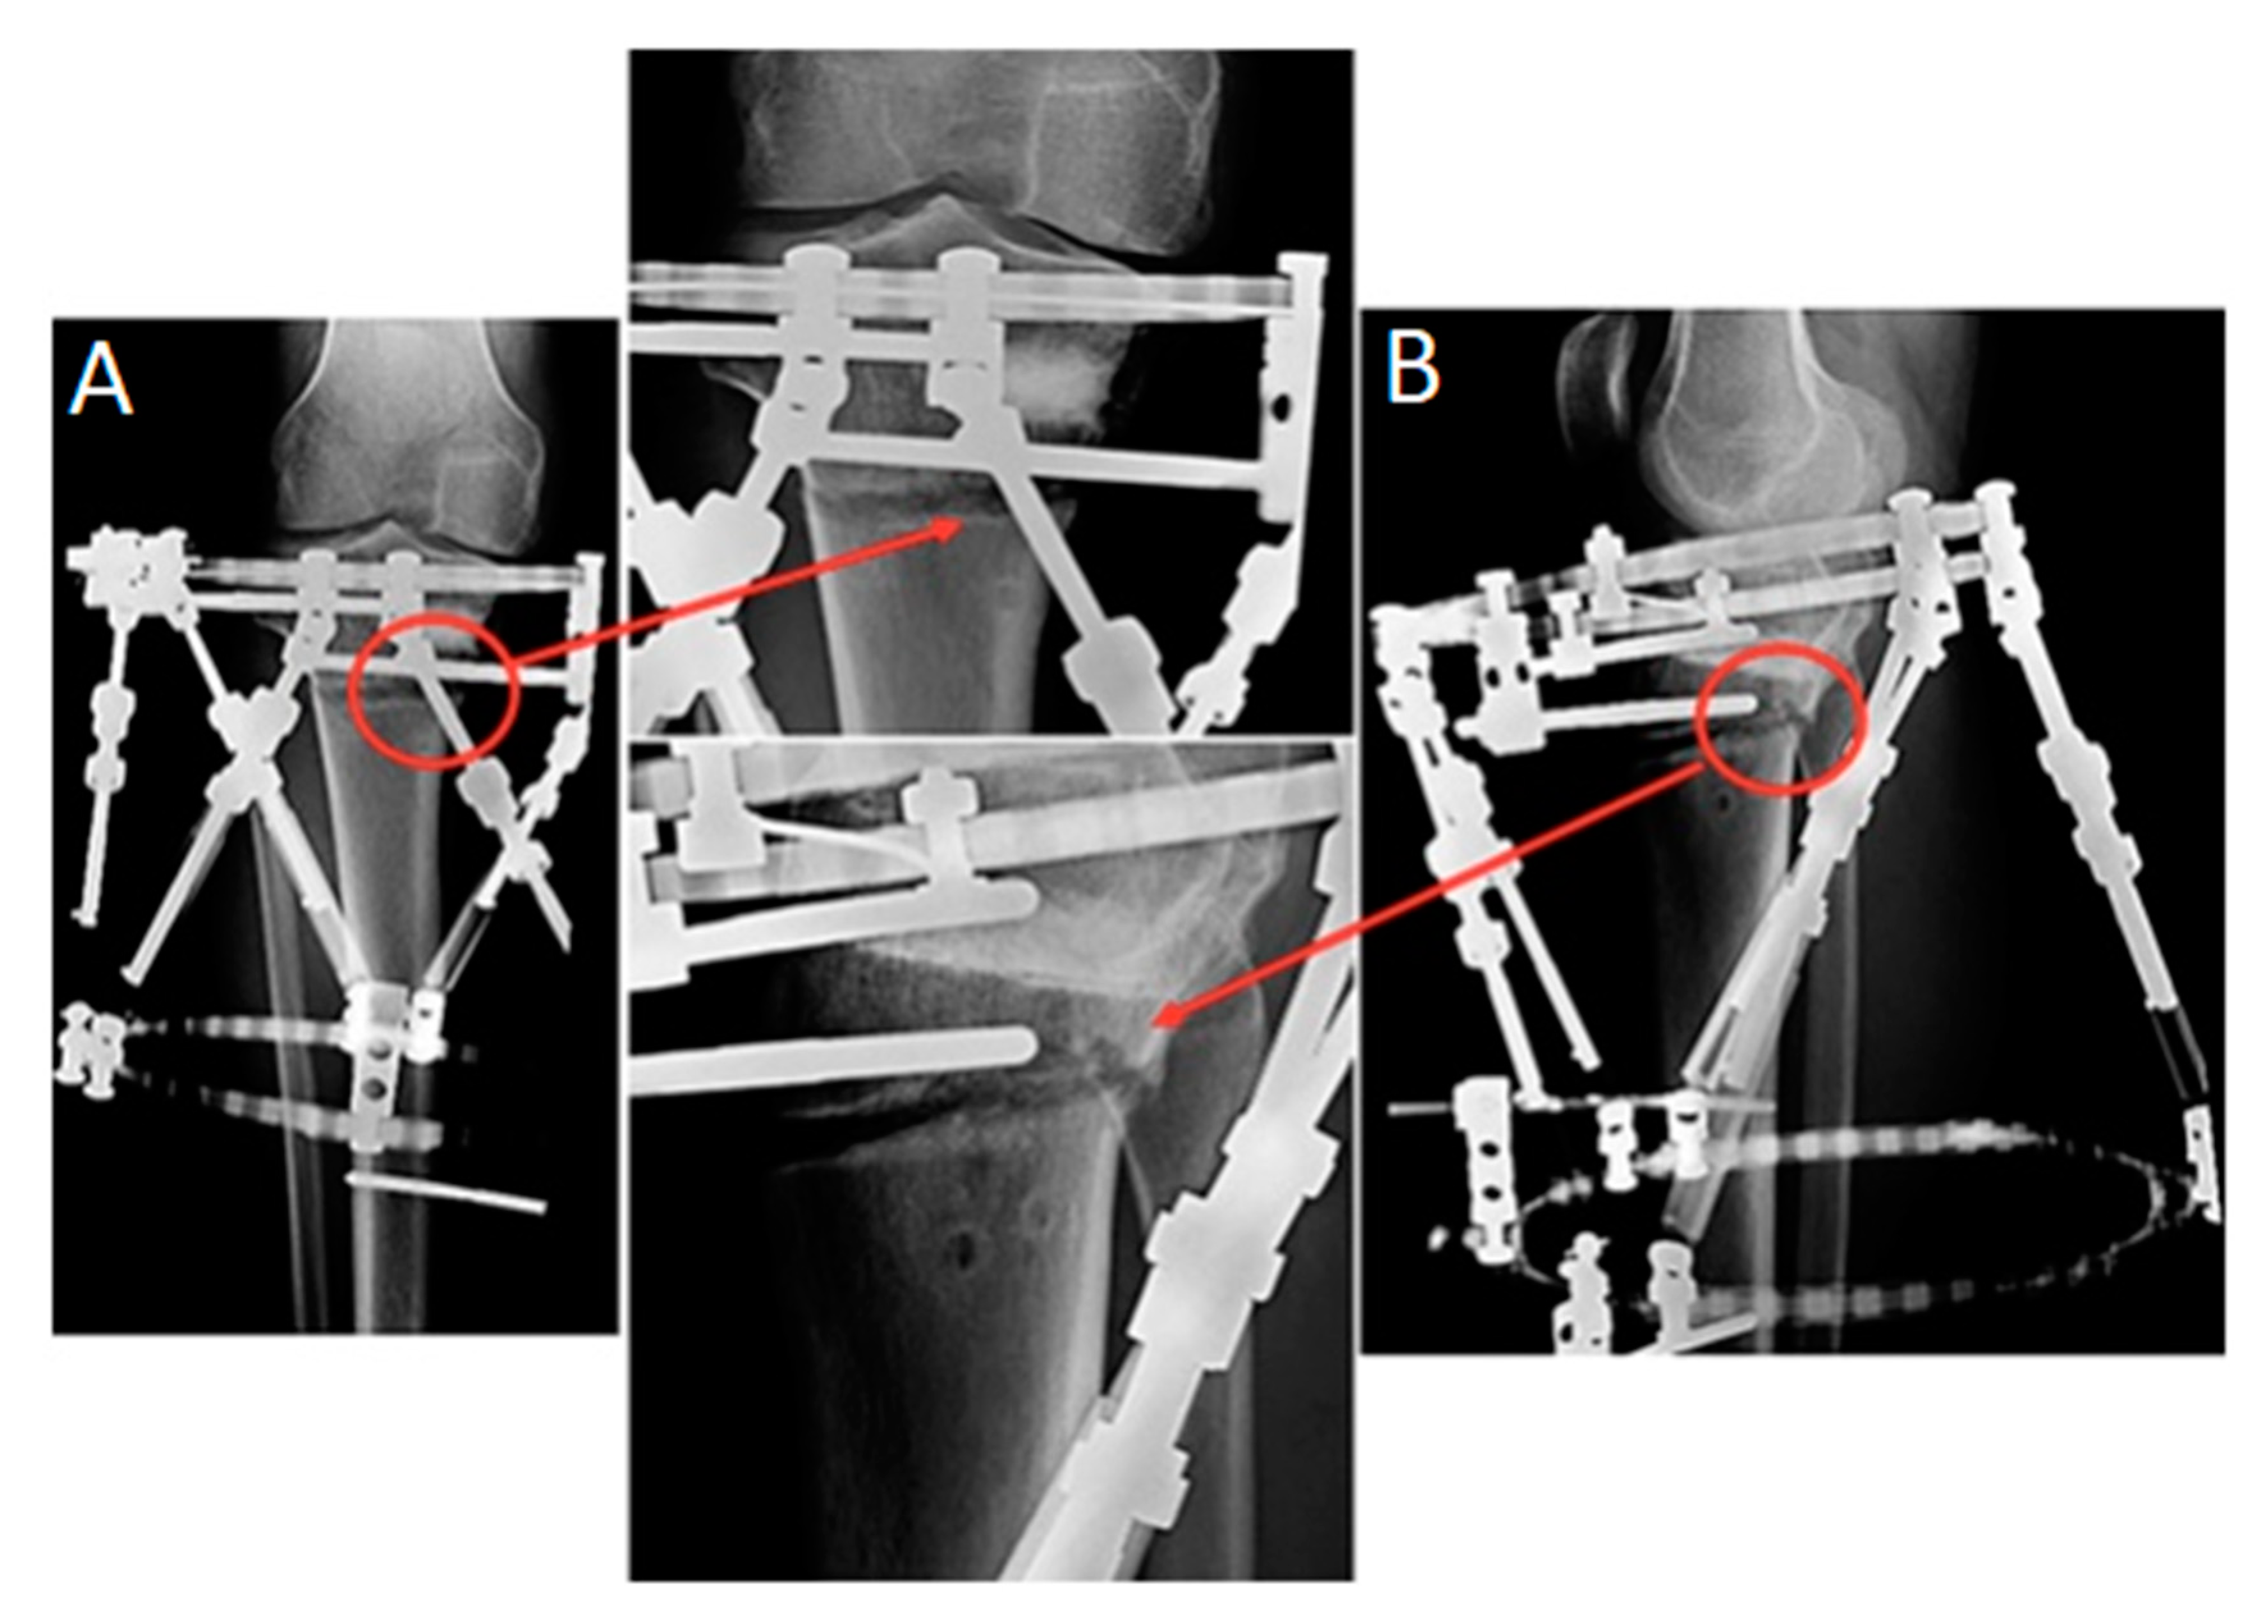

3.1. Clinical Results

3.2. Experimental Results